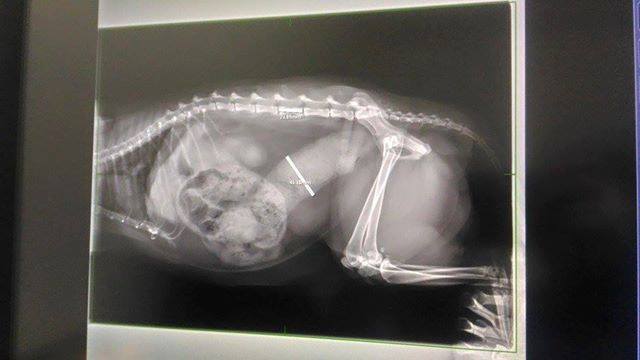

主題: 因巨結腸症無法順利排泄的小黃 申請者姓名: 臺北市支持流浪貓絕育計劃協會 花色: 申請日期: 2017-02-10 11:55:20 申請者部落格: 申請者臉書網址: 所在縣市/合作醫院: 台北市/澄諾動物醫院 治療費用: 5500元 需求人數: 13人 已結案 (2022-05-13 15:15:22) 報名人員: youngshiang(已付款)、彭小花(已付款)、Peiying Liu(已付款)、Liz x2(已付款)、Yi Ru Chen(已付款)、IRIS(已付款)、Kyra Chu(已付款)、樹下的紅果實(已付款)、陳盈年(已付款)、Missy(已付款)、kclin(已付款)、woolet(已付款)、 候補人員: 動物病情說明: 小黃原先是協會粉絲團接獲通報人通報一隻腿上長了大腫瘤的浪喵喵,

但小黃因患有巨結腸症,導致排便尚無法像一般貓咪一樣順利,

本次回診則由於小黃幾日無便

照護員見他時常蹲廁所,用盡力氣到幾乎癱軟

卻仍無法順利排便

緊急於過年期間安排就醫治療並帶回

小黃1/29回診挖大便 1/29,